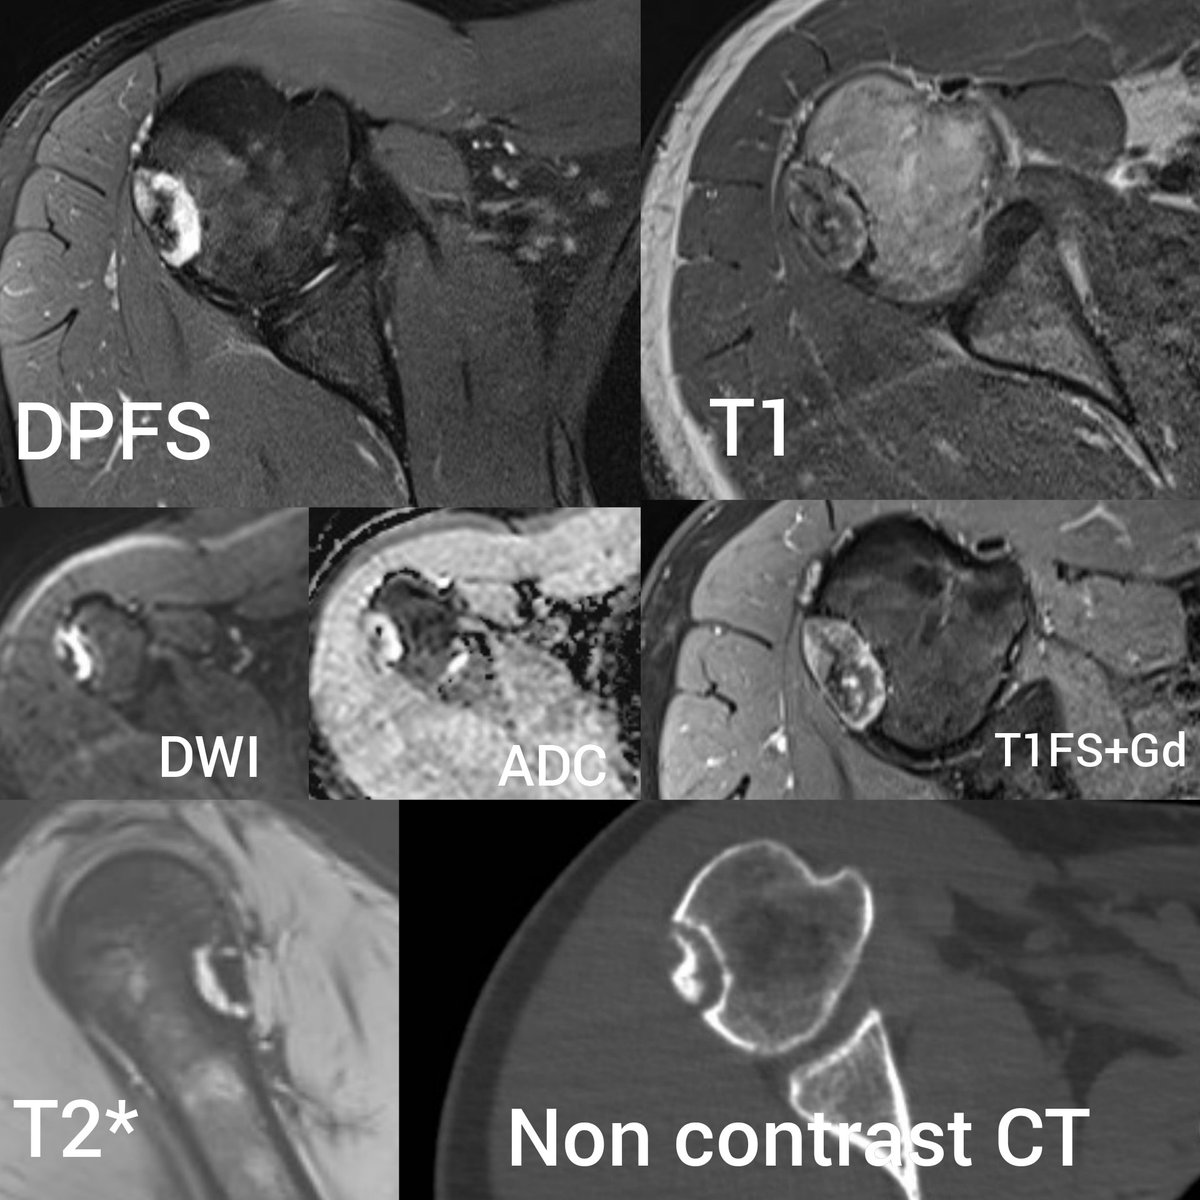

Histologically proven grade I cortical Chondrosarcoma.

#radres#foamrad#mskrad#Radiología#radiologypic.twitter.com/DOcITcDaQP